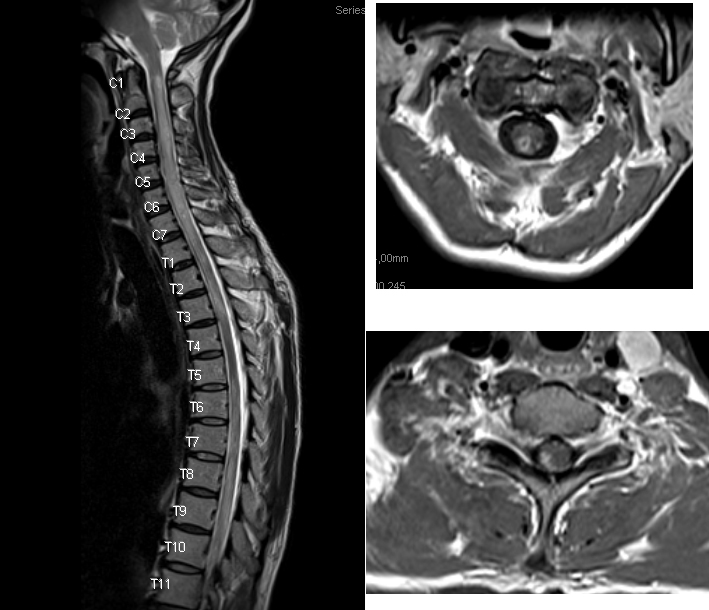

Q7: A 75-year-old woman with history of prior cervical spine decompression presented with progressive neck pain, asymmetric hand tingling, and neuropathic pain, followed by urinary incontinence and gait difficulty. Sagittal T2 weighted imaging likely shows?.